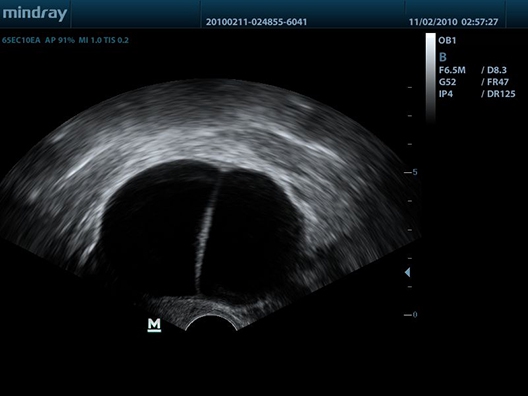

• Внутриполостной датчик Mindray 65EC10EA

Mindray DP-50 - портативный УЗИ аппарат, который является ярким представителем семейства Mindray. Он представляет собой ультракомпактное переносное устройство для проведения УЗИ-сканирования пациентов на дому или в машине скорой помощи. Аппарат оснащен черно-белым экраном и считается одним из лучших в своем классе. Он отличается высокой проникающей способностью УЗ-луча, которая обычно характерна для стационарных аппаратов.

Благодаря оптимальному 15-дюймовому экрану, впечатляющей технической оснащенности и портативной компактности, Mindray DP-50 нашел свою целевую аудиторию практически во всех сегментах современной медицины. Двухуровневая панель управления с трекболом и складывающимся экраном позволяют удобно и безопасно транспортировать систему, подобно ноутбуку. Возможности клинических исследований дополняются датчиками, которые можно приобрести дополнительно: линейные, конвексные, микроконвексные, внутриполостные, биплановые. Все зависит от ваших задач.